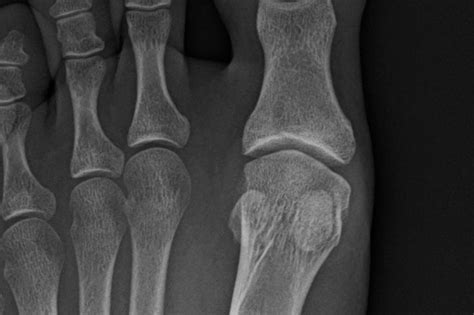

• X-Rays: X-ray images to visualize the bones and identify any fractures.

• MRI or CT Scan: Advanced imaging techniques to provide a more detailed view of the sesamoid bones and surrounding tissues.